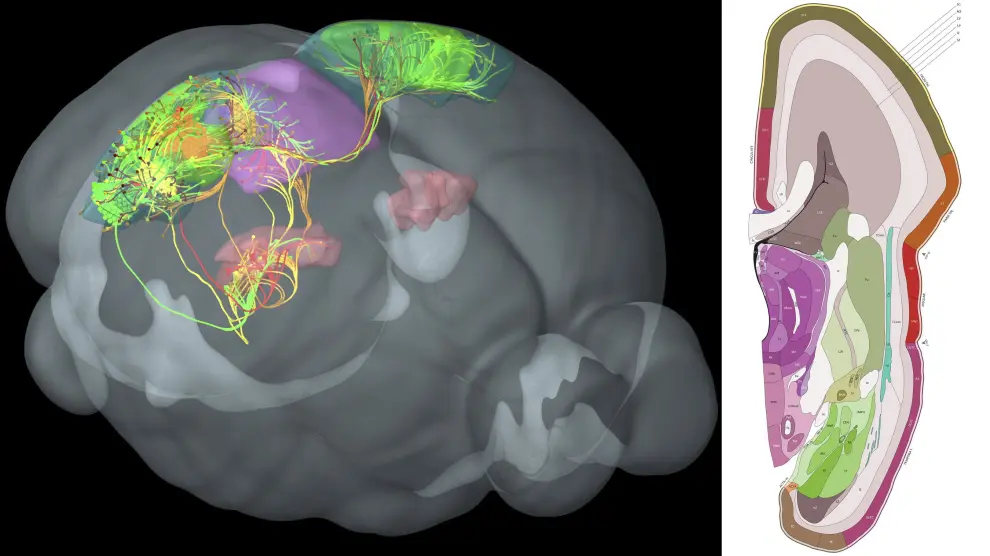

La actividad cerebral asociada con la empatía no estaba arraigada en una parte del cerebro, la forma en que las entradas sensoriales tiende a ser procesadas. Más bien, se extendió a través del cerebro e involucró múltiples regiones cerebrales. "El cerebro no es un sistema modular donde hay una región que maneja la empatía --describe Wager--. Es un proceso distribuido".

Los patrones asociados con la preocupación empática, por ejemplo, se superponen con sistemas en el cerebro asociados con valor y recompensa, como la corteza prefrontal ventromedial y la corteza orbitofrontal medial. En contraste, patrones de angustia empática se superponen con sistemas en el cerebro conocidos por reflejar, como la corteza premotora y las áreas corticales somatosensoriales primarias y secundarias, que ayudan a un individuo a simular o imaginar lo que otra persona está sintiendo o pensando.